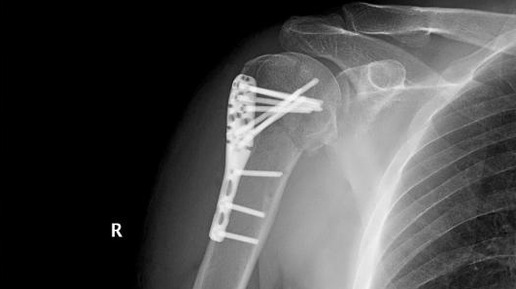

Остеосинтез плечевой кости: что нужно знать

Остеосинтез плечевой кости – это хирургическая процедура, направленная на восстановление целостности и функциональности плечевой кости после перелома. Эта методика является ключевым этапом в лечении травм и заболеваний, связанных с плечом. В данной статье мы рассмотрим основные аспекты остеосинтеза, его показания, методы, реабилитацию и возможные осложнения. Остеосинтез – это хирургическая процедура, при которой осуществляется иммобилизация и фиксация костных фрагментов, чтобы они срастались. Эта...